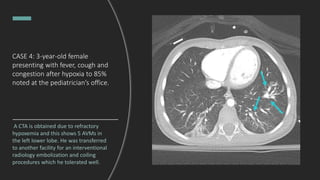

CASE 4: 3-year-old female

presenting with fever, cough and

congestion after hypoxia to 85%

noted at the pediatrician’s office.

A CTA is obtained due to refractory

hypoxemia and this shows 5 AVMs in

the left lower lobe. He was transferred

to another facility for an interventional

radiology embolization and coiling

procedures which he tolerated well.